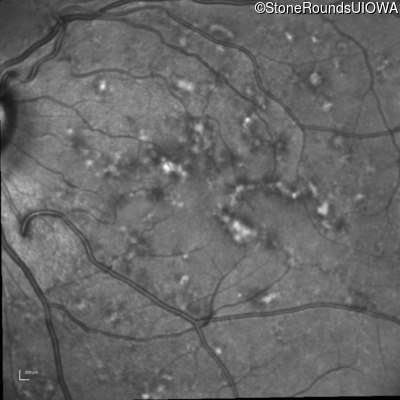

Blue Autofluorescence - Left - 20/20 -3

Exemplar